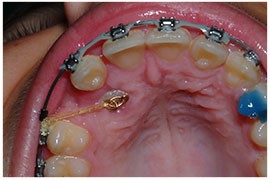

شکل- اتصال زنجیر طلایی به دندان نیش نهفته و وصل کردن زنجیر به سیم ارتودنسی براکت برای بیرون کشیده دندان نهفته صورت میگیرد.

به نگین براکت چسبانده شده به دندان نیش نهفته، یک زنجیر مینیاتوری متصل شده است. زنجیر طلایی به سیم ارتودنسی (آرچ وایر) وصل میشود. گاهی اوقات ممکن است دندان نهفته که روی آن باز شده است، به کمک بخیه کردن لثه به سقف دهان و ایجاد پنجره، کاملا نمایان بماند. اما در بیشتر مواقع بافت لثه به جایگاه قبلی خود بازگردانده شده و بخیه میشود و تنها زنجیر چسبانده شده به دندان نیمه نهفته قابل مشاهده باقی میماند و از سوراخ کوچکی در لثه بیرون میزند.

مدت کوتاهی پس از جراحی (یک تا ۱۴ روز) بیمار به ارتودنتیست مراجعه میکند. یک حلقه کشی به زنجیر متصل شده به دندان نیش وصل میشود تا دندان را به سمت خارج از لثه هدایت کند. در اینجاست که فرآیند حرکت دادن دندان به موقعیت مطلوب خود در قوس دندانی آغاز میگردد. این کار باید به دقت تحت کنترل قرار داشته باشد. این فرایند طولانی و تدریجی بوده و ممکن است یک سال طول بکشد. توجه داشته باشید هدف از درمان، بیرون زدن دندان نهفته در جایگاه درست است نه کشیدن آن. به محض که دندان به موقعیت نهایی رسید، بافت لثه اطراف آن برش خورده و بالا زده میشود تا دندانپزشک از سالم و محکم بودن آن و توانایی عملکرد مادام العمر جویدن، اطمینان حاصل نماید. در برخی شرایط به خصوص در مواردی که دندان باید مسافت طولانی را طی کند تا به موقعیت مطلوب برسد، ممکن است جراحی کوچکی در لثه انجام شود تا بر حجم بافت لثه در موقعیت جدید دندان افزوده شود تا از عملکرد نرمال آن اطمینان حاصل شود.